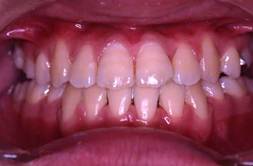

インビザラインによる矯正症例2 22歳女性

治療終了 治療開始後7か月